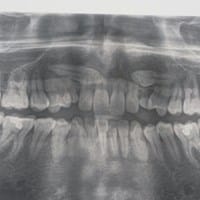

¿Es aconsejable extraer caninos superiores impactados?

Tengo 25 años y mis colmillos superiores (permanentes) nunca erupcionaron, aun tengo los colmillos superiores temporales en un estado regular, sin embargo fui a ver a un ortodoncista para encontrar una solución. El ortodoncista me pidió que me...